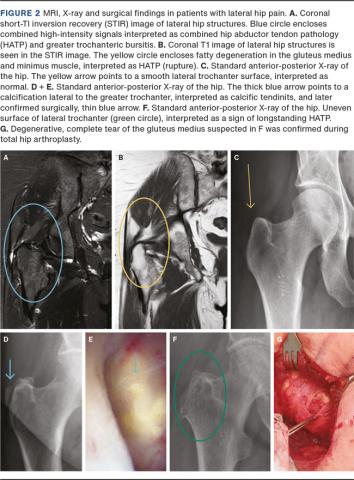

The concept of interpretation of the MRI in the study was agreed upon in consensus between CT and JL and included pre-study evaluation of five individual cases. The evaluation consisted of both “objective” findings, such as the presence of high-intensity signals, and “subjective” findings, such as the evaluators’ interpretation of the “objective” findings as the presence of HATP or bursitis. Specifically in relation to the primary outcome of this study, the presence of bursitis was evaluated on inflammatory protocols. Bursitis was defined as a clearly extra-tendinous, well-defined accumulation of high-intensity signals lateral to the greater trochanter in cases of greater trochanteric bursitis or superior to the greater trochanter in cases of subgluteal bursitis, based on the work by Cvitanic et al., Kong et al. and Dwek et al. [14, 16, 18]. Tendon discontinuity with high-intensity signals replacing the tendon structure was not defined as bursitis but as a rupture (HATP) (see Figure 1 for an example).

MRI may aid substantially in diagnosing (and differentiating) HATP in refractory LHP. Other studies have reported on the appearance of the lateral hip structures relating to the greater trochanter [15, 16]. These studies are the foundation for the approach used in the evaluation of the MRI in patients with LHP seen at our outpatient clinic. In a study by Cvitanic et al. [14] on 45 patients, the authors concluded differentiation between pathologies would be supported by the presence of a high-intensity signal, defined as hyperintensity relative to fat on T2-weighted images or iso-intensity relative to the contents of the urinary bladder on fat-suppressed T2-weighted images, and the relative location of these to the greater trochanter. We also believe that using T2 hyperintensity signals superiorly compared to laterally to the greater trochanter as a criterion for tears may be important information in the preoperative assessment of the abductor tendons of the hips and in determining whether surgical repair is indicated. If a high-intensity area is present superior to the top of the greater trochanter, this is strongly indicative of a tear (see Figure 1).